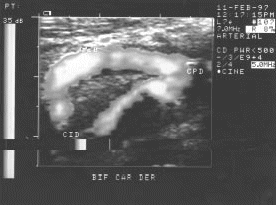

Figura 19.- Duplex color de un caso de estenosis severa. Velocidad media 1.58 m/seg.